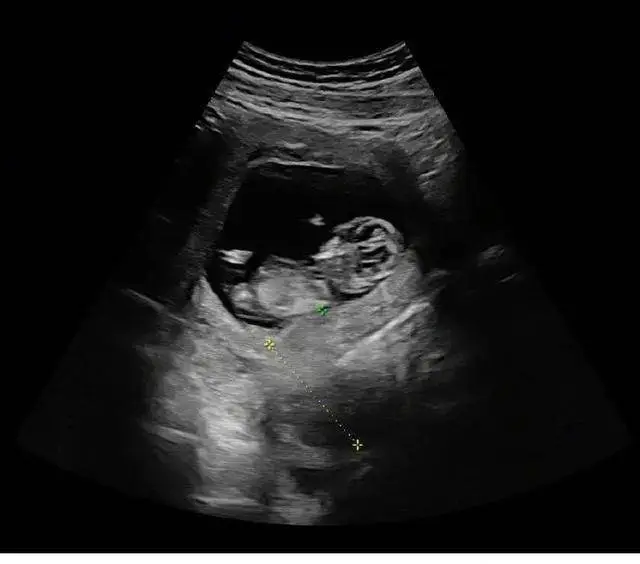

可能是突然来了一个小生命,升级成为了爸爸妈妈,太开心了,之后第二张就送上了小宝宝的照片,在肚子里只有三个月,样子还看得不是很清楚,但是看到爸爸妈妈的长相就知道,这个小宝宝长大,也一定非常好看,男宝宝一定很帅气,女宝宝一定很漂亮。